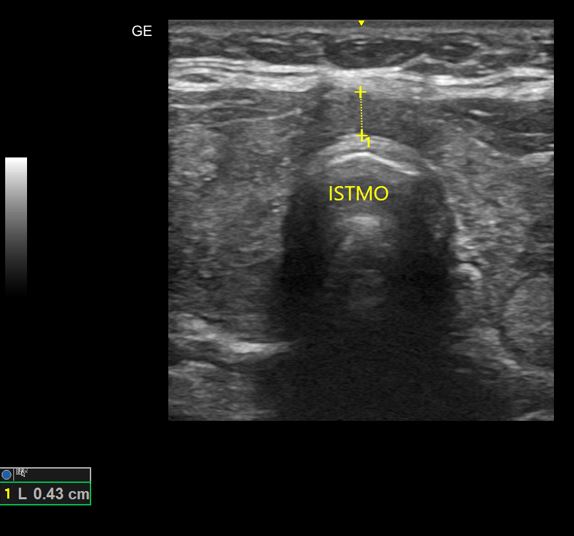

Nódulos de Tireoide

USG de nódulos benignos